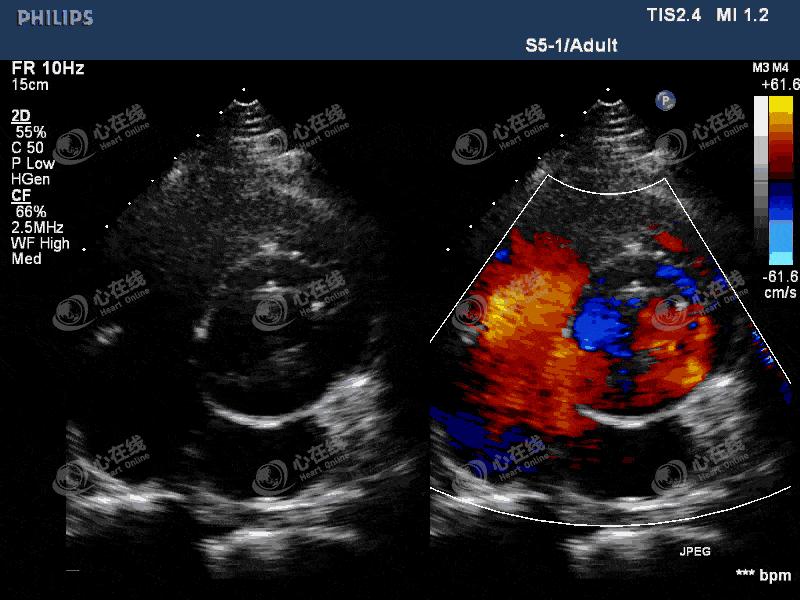

【超声心动图】

图2 左室长轴切面:彩色多普勒示,机械瓣瓣环外侧可见中量血流信号进入左室,另可见机械瓣中心性反流信号。主动脉根部膜样回声破口处可见血流信号,来自主动脉,并穿梭于该无回声区内。